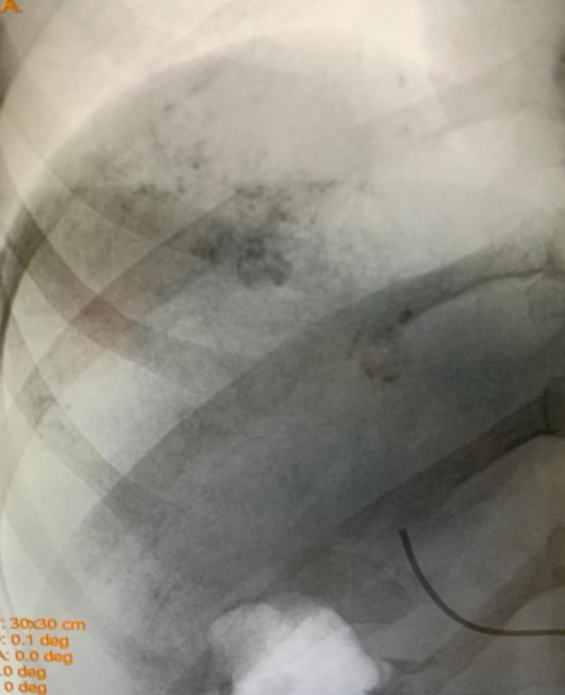

В 84,75 % (n = 50) случаев были диагностированы кавернозные гемангиомы, которые относятся к малососудистым образованиям, и лишь в редких случаях внутри гемангиомы регистрировали артериальный спектр кровотока при наличии афферентной васкуляризации вокруг. Кавернозные гемангиомы имели в своей неоднородной структуре мелкие и крупные полости, визуализируемые как эхонегативные или гипоэхогенные участки, форма которых чаще была неправильная, а допплеровские методики были малоинформативными (рис. 1).

Рис. 1. Ультразвуковое изображение кавернозной гемангиомы правой доли печени